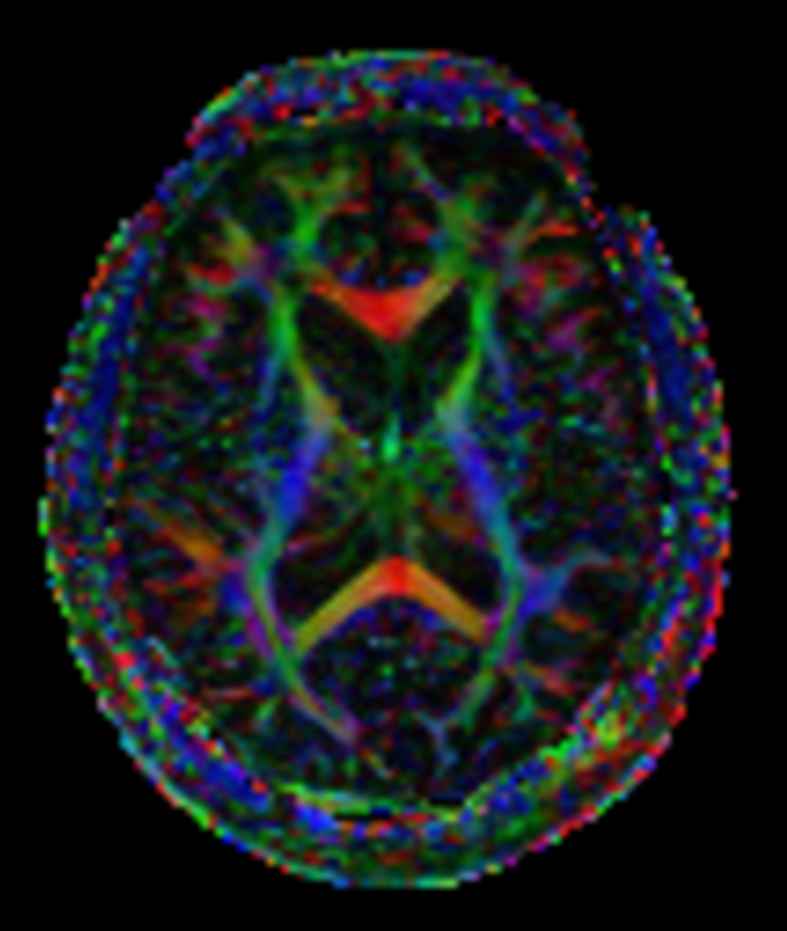

DTI b800 MultiBand SENSE 32 directions

DTI b800 MultiBand SENSE 32 directions (FA map)